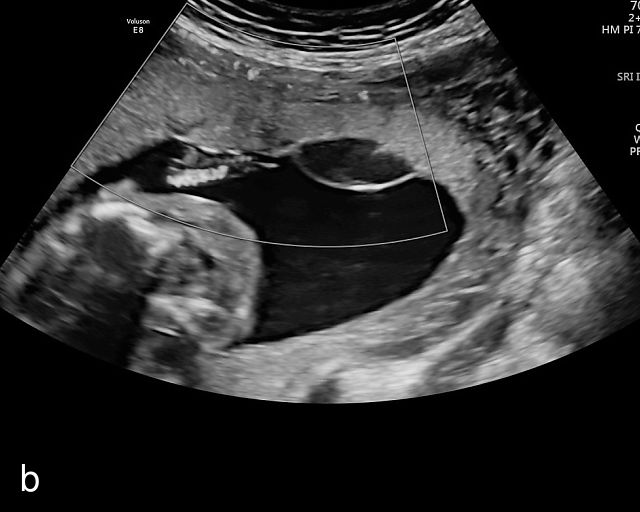

In the early first trimester, trophoblastic tissue appears as an echogenic ring encircling the gestational sac (Figure 1a). By the late first trimester, the placenta becomes recognizable as a distinct structure on ultrasound (Figure 1b). Initially, it presents as a homogeneous echogenic mass (Figure 1b–d) but undergoes progressive differentiation, becoming more heterogeneous as pregnancy advances from the second to third trimester (Figure 1e–g). By the third trimester, cotyledons become discernible, and in the late third trimester, calcifications frequently appear basally and around the cotyledons (Figure 1g).

1

Ultrasound images of development of the placenta (P/p). (a) Trophoblastic tissue appearing as an echogenic ring surrounding the gestational sac at 6 weeks' gestation. (b) Placenta at 12 weeks has become a discrete, uniformly echogenic mass. (c) Placenta at 17 weeks. (d) Placenta at 20 weeks. (e) Placenta at 27 weeks. (f) Placenta at 33 weeks. Increasingly, differentiation and heterogeneous appearance is seen, with demarcation of the cotyledons. Basal calcifications are beginning to appear. (g) Placenta at 40 weeks, showing a distinctly heterogeneous appearance, with clear demarcation of the cotyledons and presence of calcifications.